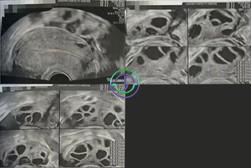

促排第 8 天 — 多个卵泡已逐渐发育,尺寸渐渐增大

超声结果

右侧卵巢:卵泡大小 17,17,17,17,16,12,12,12,11,10,10 mm → 共 11 个卵泡

左侧卵巢:卵泡大小 17,16,16,15,15,14,14,13,12,11,10,10 mm → 共 12 个卵泡